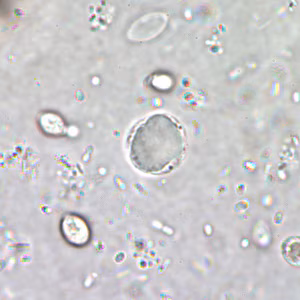

A 29-year-old man went to a local health clinic with complaints of intermittent diarrhea for a few months. He did not report any other symptoms but said he had difficulty sleeping sometimes. A stool specimen was collected and preserved in both 10% formalin and polyvinyl-alcohol (PVA). An ova and parasite (O & P) examination was performed. Figure A shows what was seen on a concentrated wet mount preparation, and Figure B shows what was seen on a wet mount stained with iodine. Figures C and D show what was seen on a trichrome stained smear made from the PVA preserved specimen. Objects measured 7 to 10 µm in diameter. What is your diagnosis? Based on what criteria?

Figure A